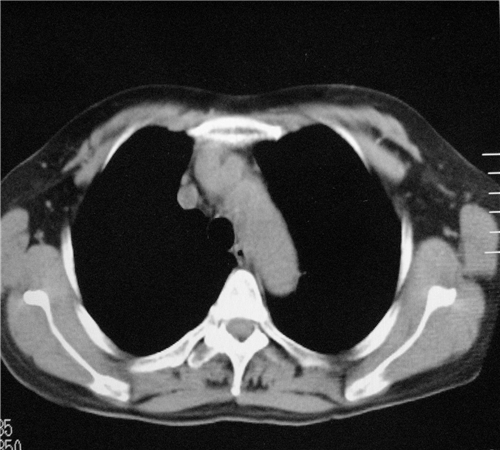

标题: CT26849:女67岁反复胸痛两天余,临床考虑夹层。 [打印本页]

标题: CT26849:女67岁反复胸痛两天余,临床考虑夹层。

右肺感染,未见夹层。

既然考虑夹层,建议强化!另:右下肺感染!

1)右肺感染性病变。2)建议行ct增强扫描或mri检查排除主动脉夹层。

双下肺感染,右侧显著。有无夹层,增强扫描后再诊断。

1. 感染性病变,2.未见夹层,3.食道未见异常。

1.考虑双肺感染,右侧为重;2.建议ct增强或mri排除主动脉夹层

平扫未见确切夹层征,建议必要时增强扫描或mri检查。